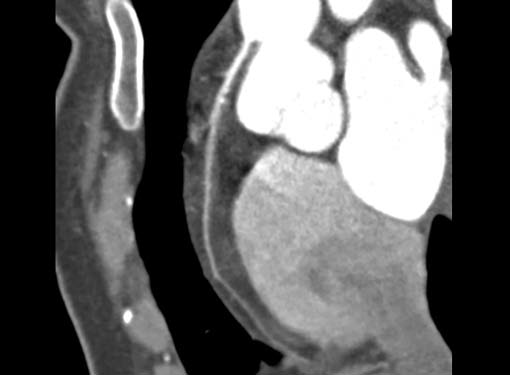

CT is the preferred tool of investigation of coronary bypass grafts (Fig. 9). Reversed saphenous vein grafts (SVGs) are optimally studied consistently. Anastomotic sites are studied effectively. However, distal anastomosis of venous graft to obtuse marginal branch (OM) is relatively difficult to evaluate because of diminishing caliber of native vessel. Arterial grafts pose a small challenge due to artifacts of associated surgical clips (Figs 10A and B). Ostium and proximal part of graft are assessed well. However, distal anastomotic site may be difficult to assess on occasions. RIMA graft, posterior descending artery (PDA) graft, gastroepiploic artery graft can also be studied. Stenosed venous grafts

can be stented and the same can be evaluated by CT (Fig. 11). Like native RCA, RCA grafts (Figs 12A and B) are more susceptible to motion artifacts when compared to LAD and OM grafts. Catheter angiogram can be used to answer specific queries after CT angiogram.